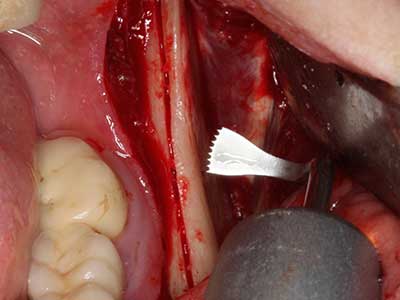

Piezosurgery has additional advantages when harvesting bone blocks. In addition to the high precision with osteotomy described above, the use of the thin saw tips specifically minimizes loss of material. Greater loss of material during harvesting can be expected with the thicker instrument tips, particularly when using Lindemann drills (Lakshmiganthan, Gokulanathan et al. 2012). The basal separation, which is necessary particularly for retromolar block transplants, is simplified by specially designed rectangular saws, with the result that piezosurgery is viewed as a precise, simple and safe procedure for harvesting retromolar bone blocks (Happe 2007) (Fig. 1-12).